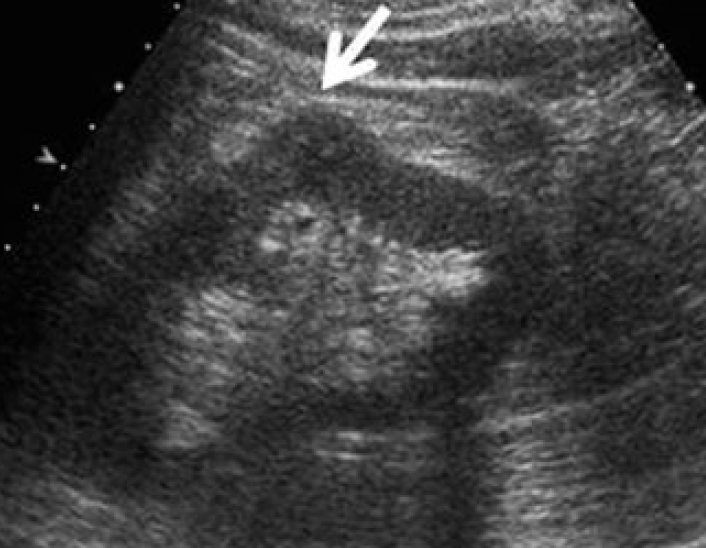

2-Kidney hump

تسمى أيضا Dromedary hump وهي مثل البروز في شكل parenchyma الكلية كسنام الجمل. سماكتها يجب أن تتناسق مع بقية parenchyma المحيطة بدون بروز. هي شائعة تحديدا في الكلية اليسرى وذلك لأن التغير يحدث في مرحلة تطور الجنين وضغط الطحال على الكلية.

في هذه الحالات يجب التأكد من السماكة (متناسقة) و echogenicity (غير مختلفة) و colour Doppler (طبيعية).